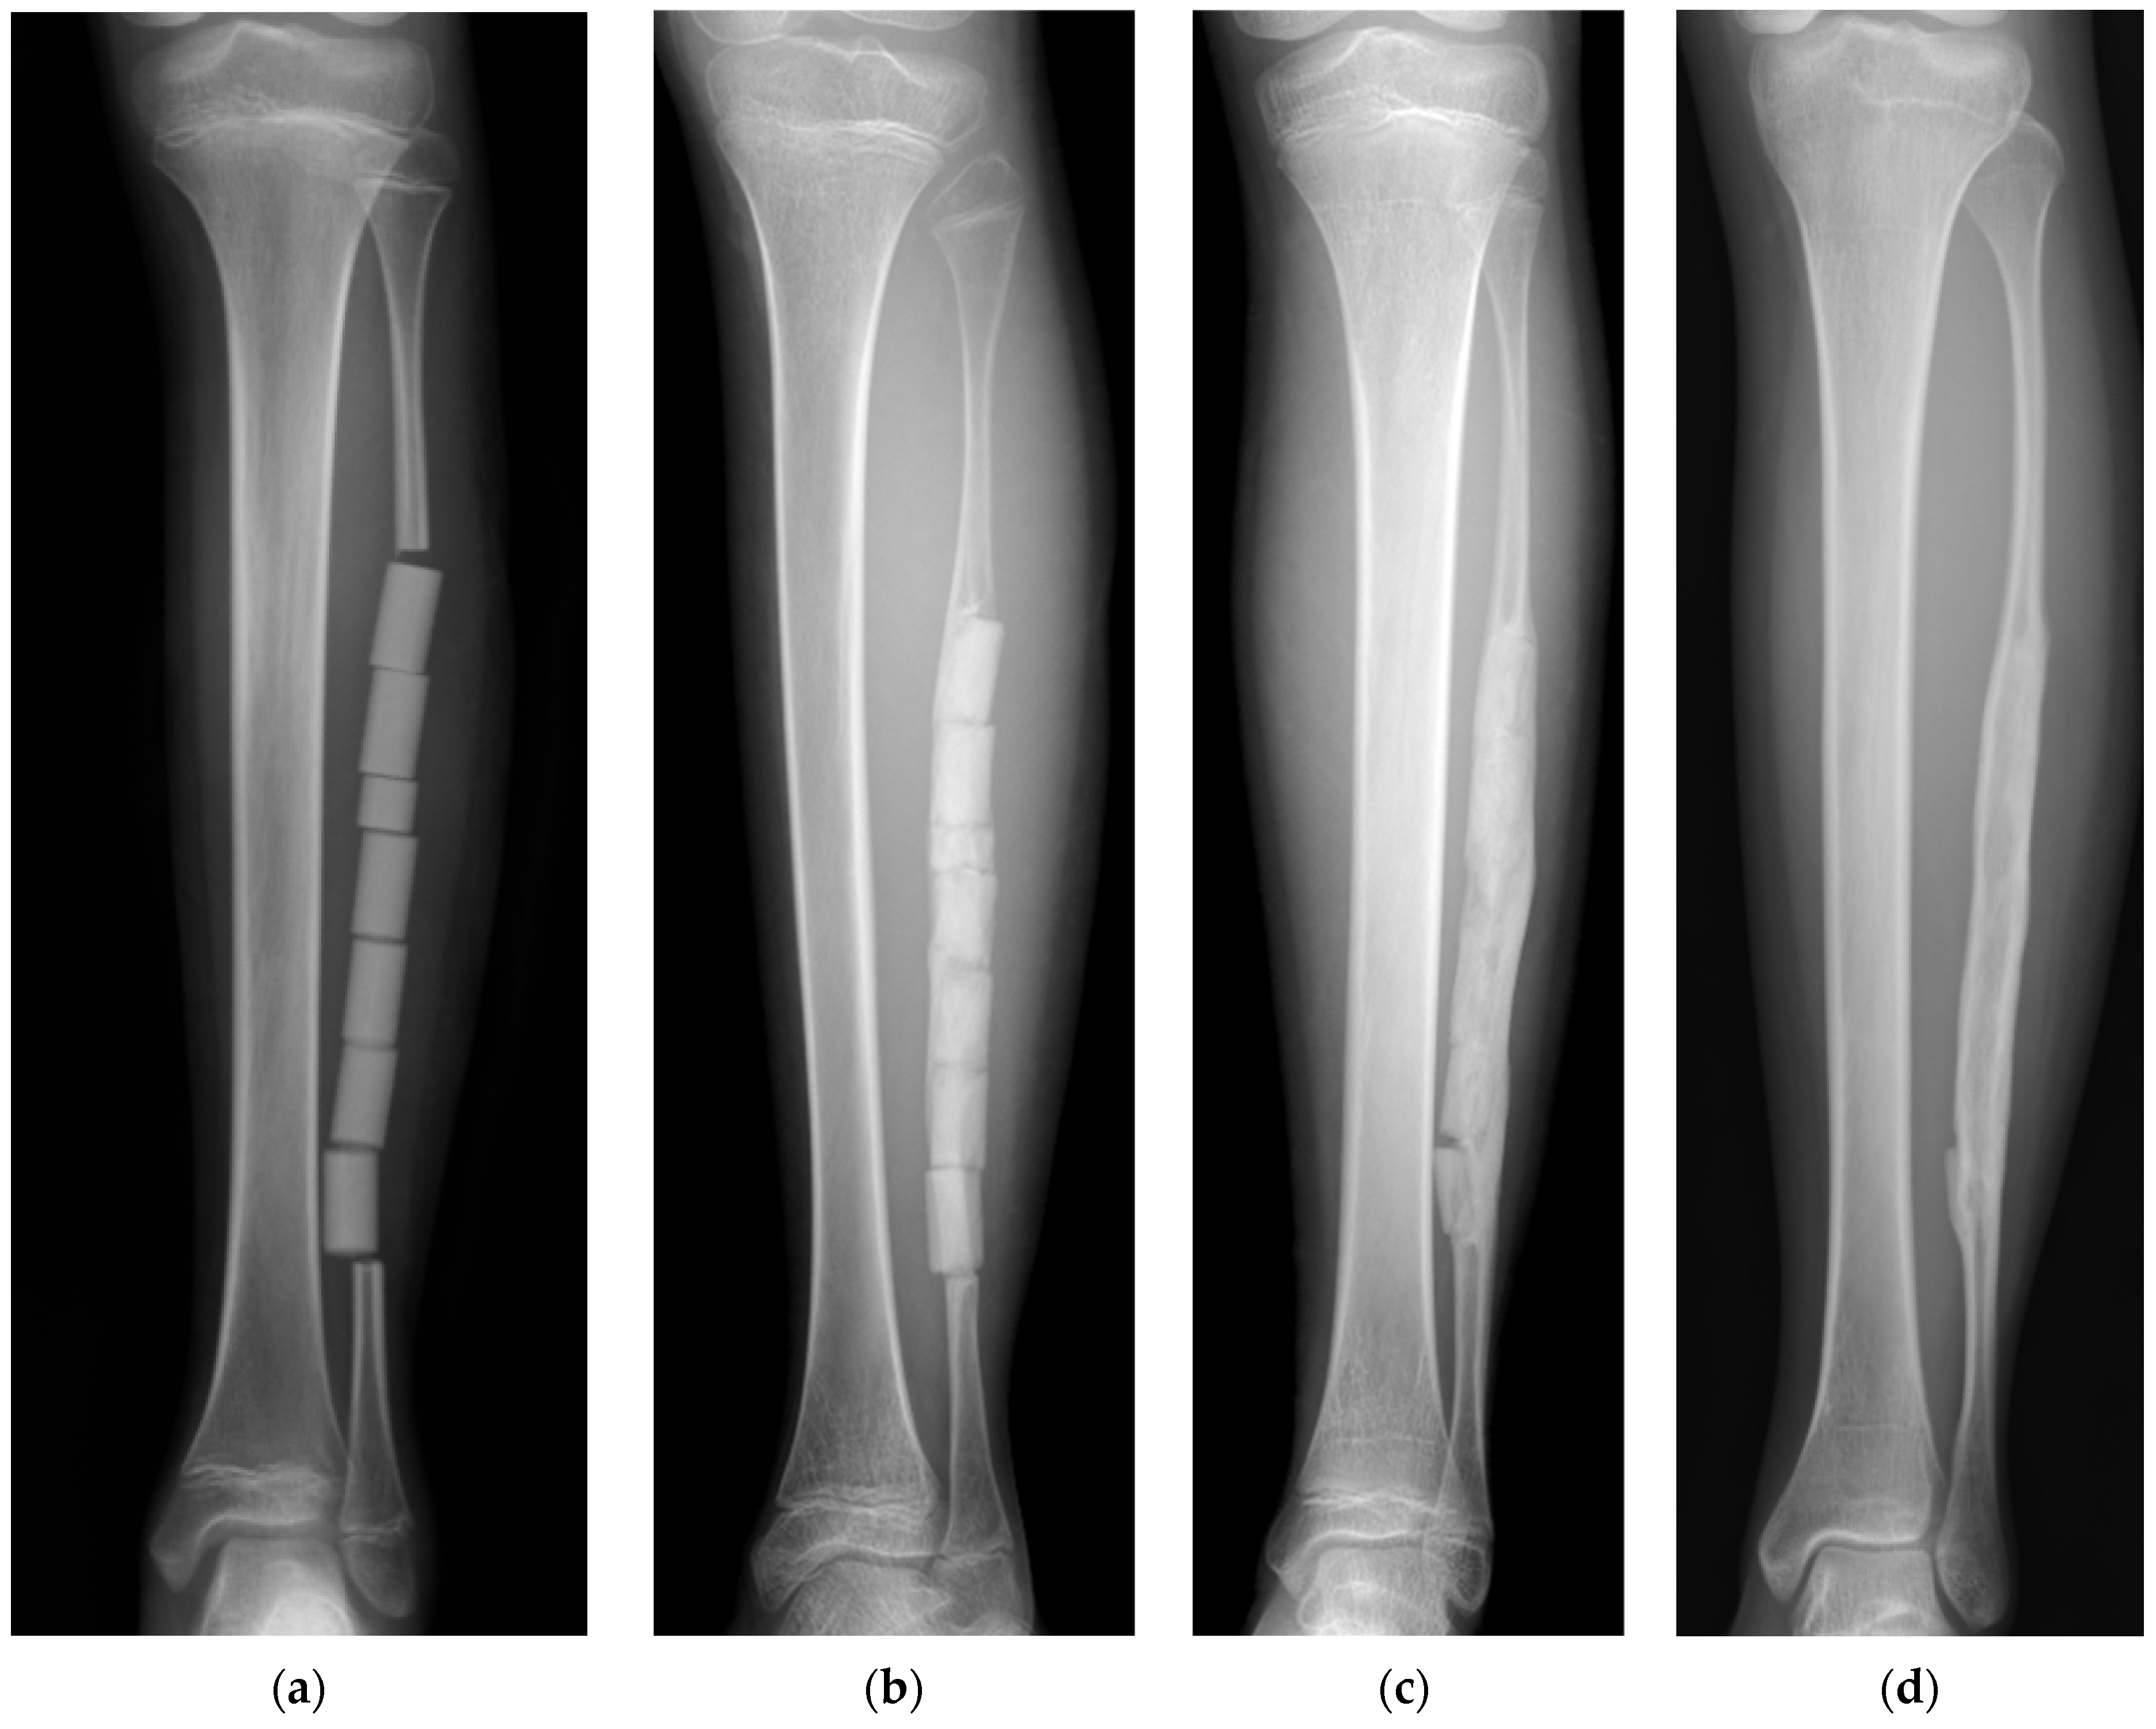

Figure 3. Radiographs of UDPHAp implantation in a segmental bone defect of the fibula after harvesting [7]. (a) Column-shaped UDPHAp implants were visible one week after surgery. Full weight bearing on the left leg was not allowed within 6 weeks after surgery to stabilize the pelvic reconstruction. The patient returned to normal daily activities 6 months postoperatively due to postoperative chemotherapy; (b) the resorption of the implanted UDPHAp was detected, and partial remodeling of the marrow space was seen 11 months after surgery; (c) new bone formation and resorption of implanted UDPHAp had progressed 2.5 years after surgery; (d) the complete resorption of implanted UDPHAp and clear formation of cortex and marrow were observed 12 years after surgery.

In a pediatric patient with Ewing’s sarcoma of the pelvis, a free fibular graft was harvested from the left leg for pelvic reconstruction after tumor resection [7]. After fibular resection, the defect was filled with column-shaped UDPHAp implants (Figure 3). The remaining periosteum was sutured to cover the implanted UDPHAp as completely as possible. A plain radiograph taken one month after surgery showed new bone formation in the gap between the remaining proximal fibula and the implanted UDPHAp and a callus-like structure around the centrally implanted UDPHAp. The resorption of the implanted UDPHAp was noted, and the partial remodeling of the marrow cavity was observed 11 months after surgery. There was good regeneration of the fibula with bone cortex and marrow 2.5 years after surgery. In addition, the bony continuity of the fibula in the segmental defect was complete after harvesting. The implanted UDPHAp was resorbed over time, and clear formation of cortex and marrow was observed in the resected part of the fibula at the final follow-up (12 years). The implantation of UDPHAp into the fibular defect did not cause any complications related to graft harvesting or UDPHAp implantation. The patient achieved good postoperative function and was able to walk without crutches and participate in sports activities. UDPHAp is a good bone substitute for filling segmental defects in the fibula after graft harvesting.